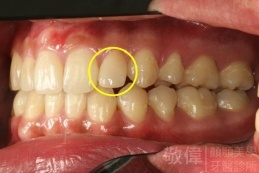

| 8 | 前牙美容 | 快速矯正之美容晶瓷貼片及晶鑽瓷冠 | ||